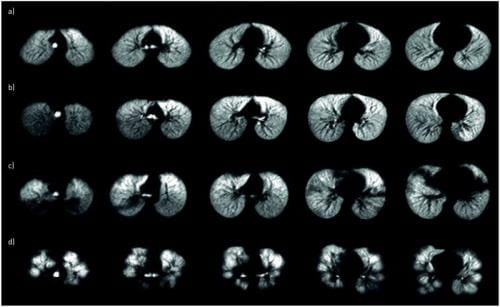

Hyperpolarized Xe gas is emerging as an inhaled contrast agent of assessing pediatric lung disease, and our group is working to improve all aspects of Xe MRI including engineering solutions for faster Xe gas production with higher MRI signal, designing MRI pulse sequences for faster acquisition with shorter breath-holds, and adapting Xe MRI techniques for younger children.

Our team was the first to demonstrate Xe MRI was safe in children and feasible even in children who are unable to perform spirometry, the clinical gold-standard test for lung disease. We recently demonstrated that Xe gas-transfer MRI, a technique that provides regional measurement of pulmonary gas exchange in adults, was feasible in pediatric populations and detected membrane-uptake and red-blood cell transfer abnormalities in children with lung disease.